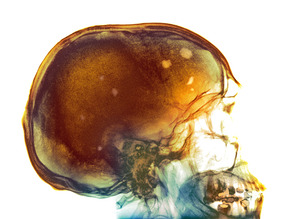

Who Nose?